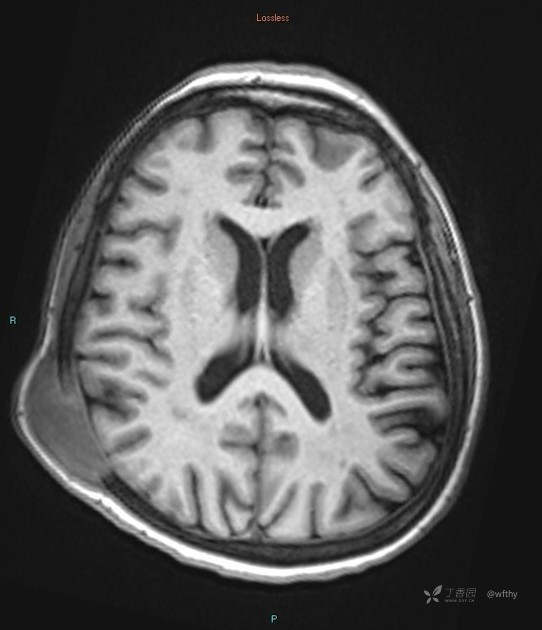

病例女65,头部肿块